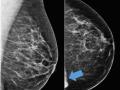

Sternal muscle simulating asymmetry on mammography

Mammography